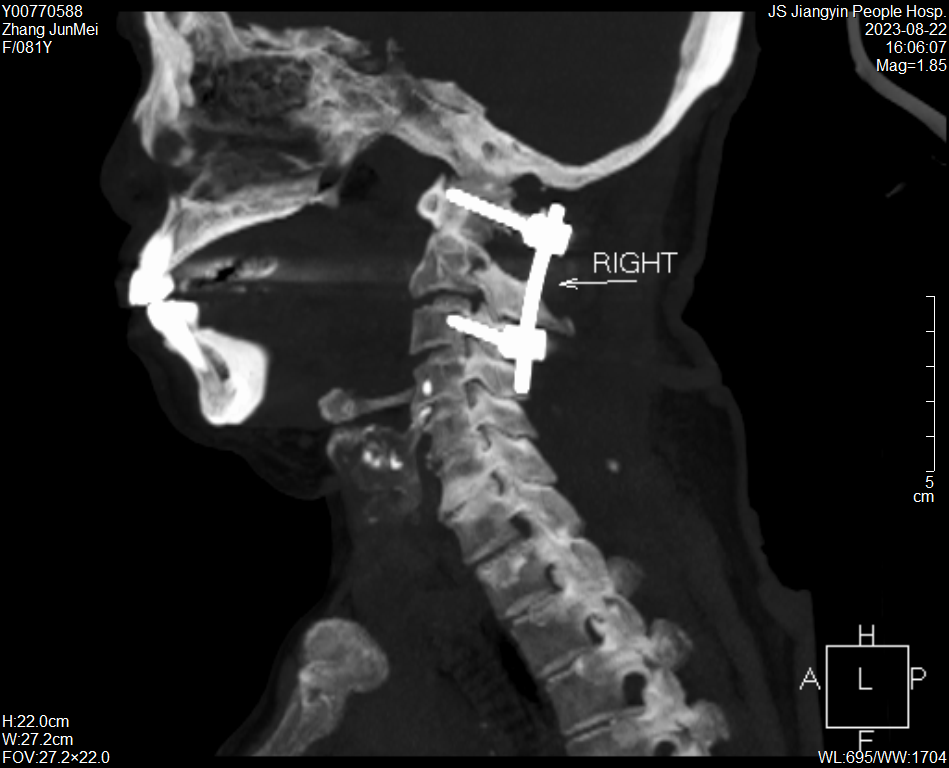

張奶奶術后CT

術后第2天,老人就佩戴頸椎支具下床活動。目前,張奶奶病情恢復良好,穩步康復中。